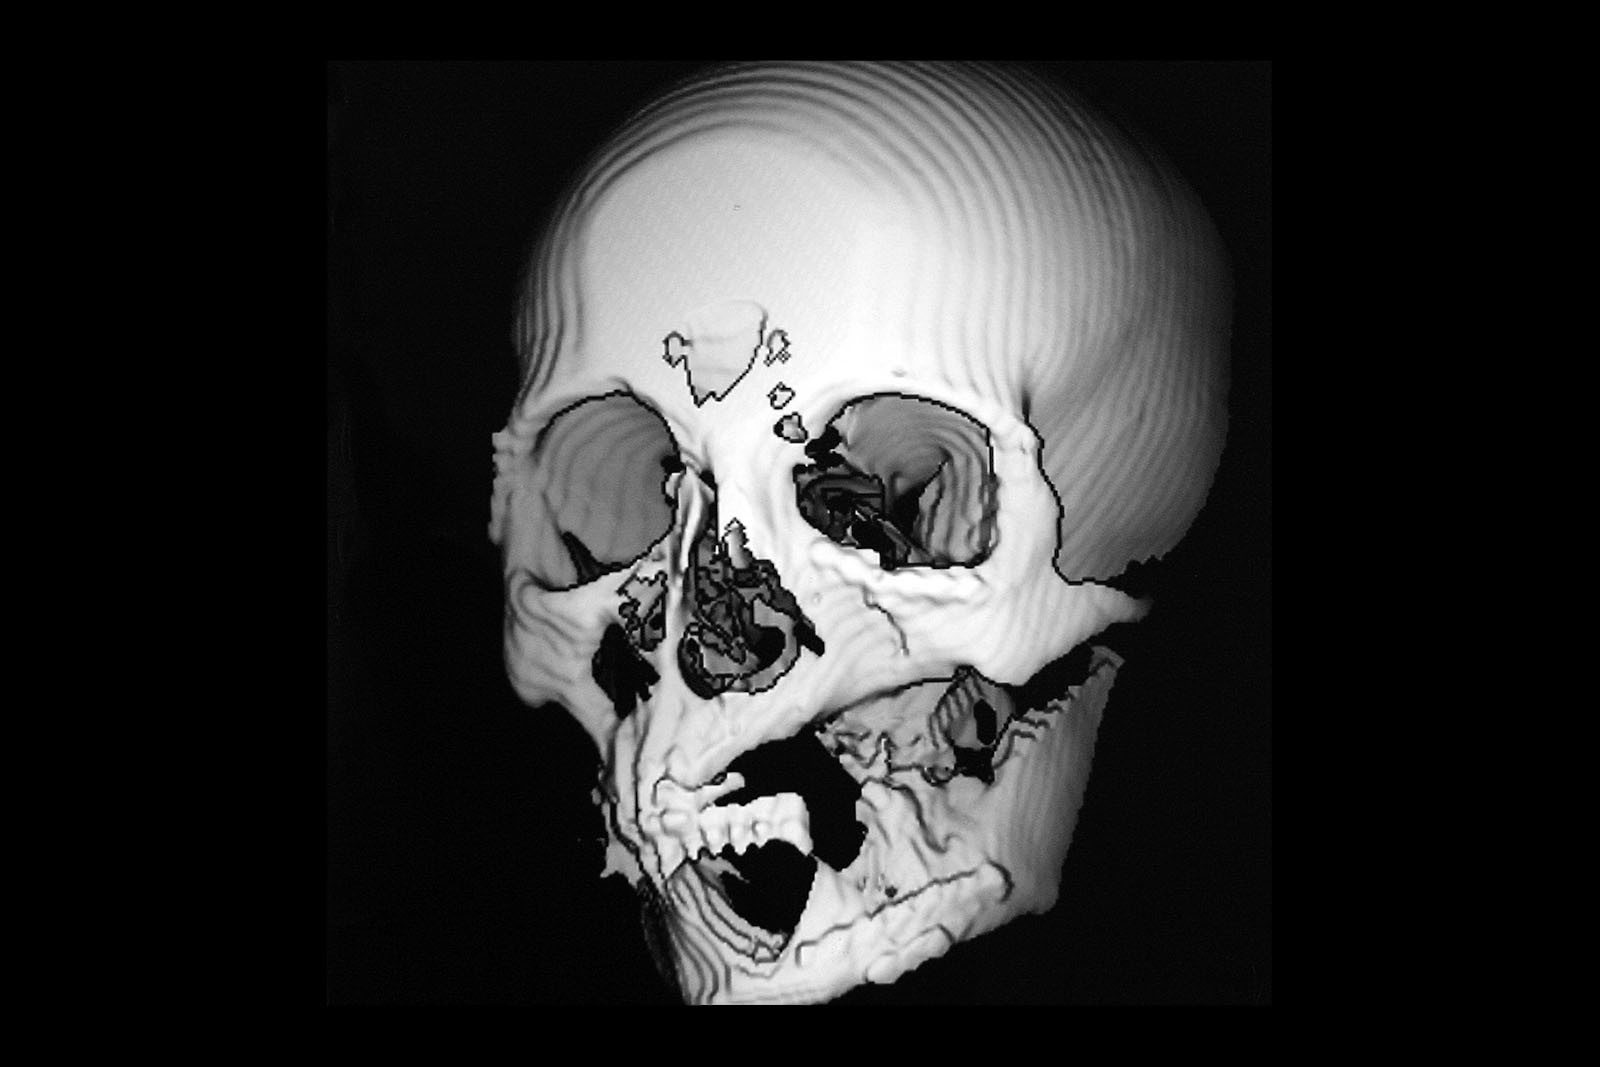

Zewnątrzustne protezy szczękowo-twarzowe, tzw. epitezy, mają zadanie przywrócenia funkcji i wyglądu twarzy człowieka, który utracił jej elementy, np. nos, oko, ucho, policzek, szczękę, w wyniku zabiegów onkologicznych lub innych zabiegów z zakresu chirurgii szczękowo-twarzowej lub chirurgii stomatologicznej. Są to tzw. ektoprotezy twarzy. Wykonywane są z akrylu oraz miękkiego silikonu, który imituje funkcję skóry oraz błony śluzowej.

Wewnątrzustne uzupełnienia protetyczne obturujące ubytki po resekcjach kości twarzoczaszki z powodu nowotworów dna jamy ustnej, zatok szczękowych oraz innych istotnych obszarów twarzoczaszki są to zwykle akrylowe protezy z obturatorami, które mocowane są na zasadzie prostego przylegania do podłoża lub na implantach osteointegrujących wszczepionych w okoliczne struktury kostne. Ciągle jednak odtwórcza chirurgia szczękowo-twarzowa, jak i chirurgia plastyczna jest pomocna w odtwarzaniu utraconych elementów anatomii twarzoczaszki. Zabiegi z zakresu chirurgii rekonstrukcyjnej i mikrochirurgii wykonywane są na sali operacyjnej i wymagają zaplecza szpitalnego.

W ocenie wewnątrzstawowych patologii pomocna jest diagnostyka obrazowa. Konwencjonalne zdjęcia radiologiczne OPG, tomografia komputerowa oraz stożkowa tomografia komputerowa CBCT pozwalają na ocenę elementów kostnych stawu skroniowo-żuchwowego. Ocenę tkanek miękkich zlokalizowanych wewnątrzstawowo umożliwia rezonans magnetyczny NMR.